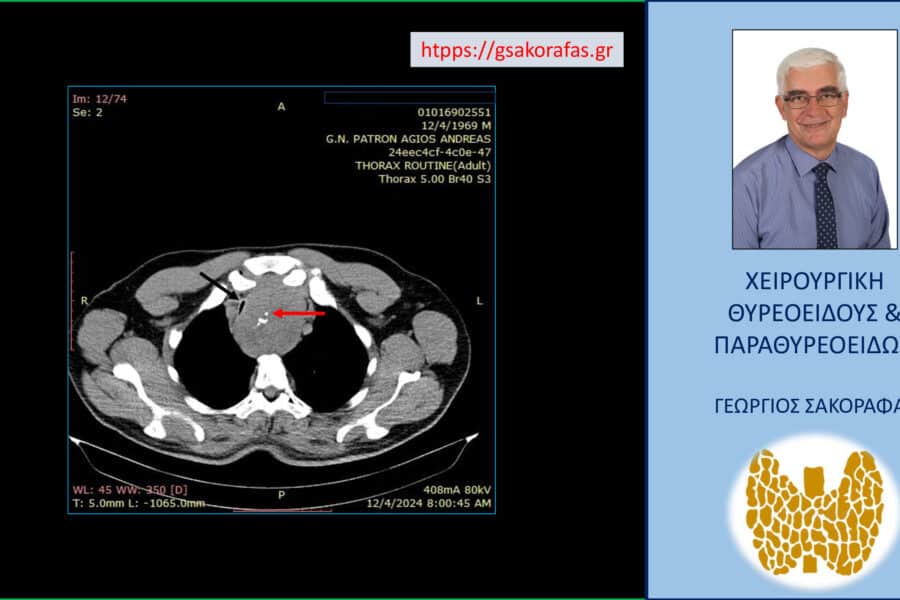

Όζοι θυρεοειδούς και συμπληρωματική θυρεοειδεκτομή (completion thyroidectomy) – με αφορμή ασθενή μας Παρουσίαση ασθενούς Αιτία…